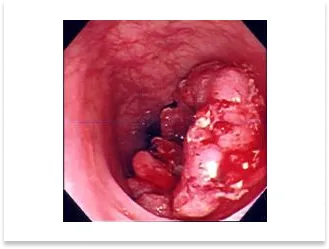

胃体上部の隆起型進行癌症例

術前内視鏡写真